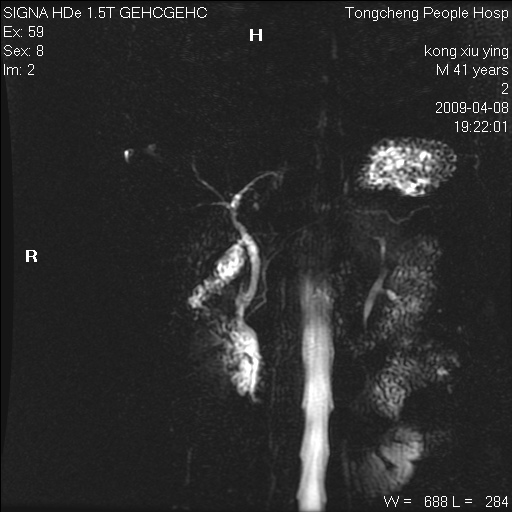

标题: CL1008:【经典】胆囊石榴籽样结石。

女,41岁。健康体检——彩超提示:胆囊显示不清。平素健康,无不适感。

腹部mr扫描及mrcp,图像如下: